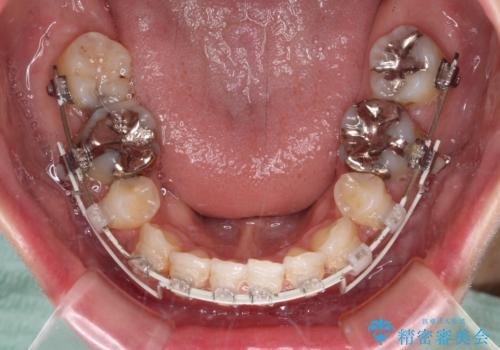

上下左右第一小臼歯4本を抜歯し、ワイヤー装置にて口元を引っ込めるよう矯正治療を行うこととしました。

奥歯が前方に傾斜していることで深く咬みこむ(ディープバイト)状態であったので、なかなか抜歯したスペースが閉じず、様々な方法でディープバイトを改善しながら治療を進めていくこととなりました。